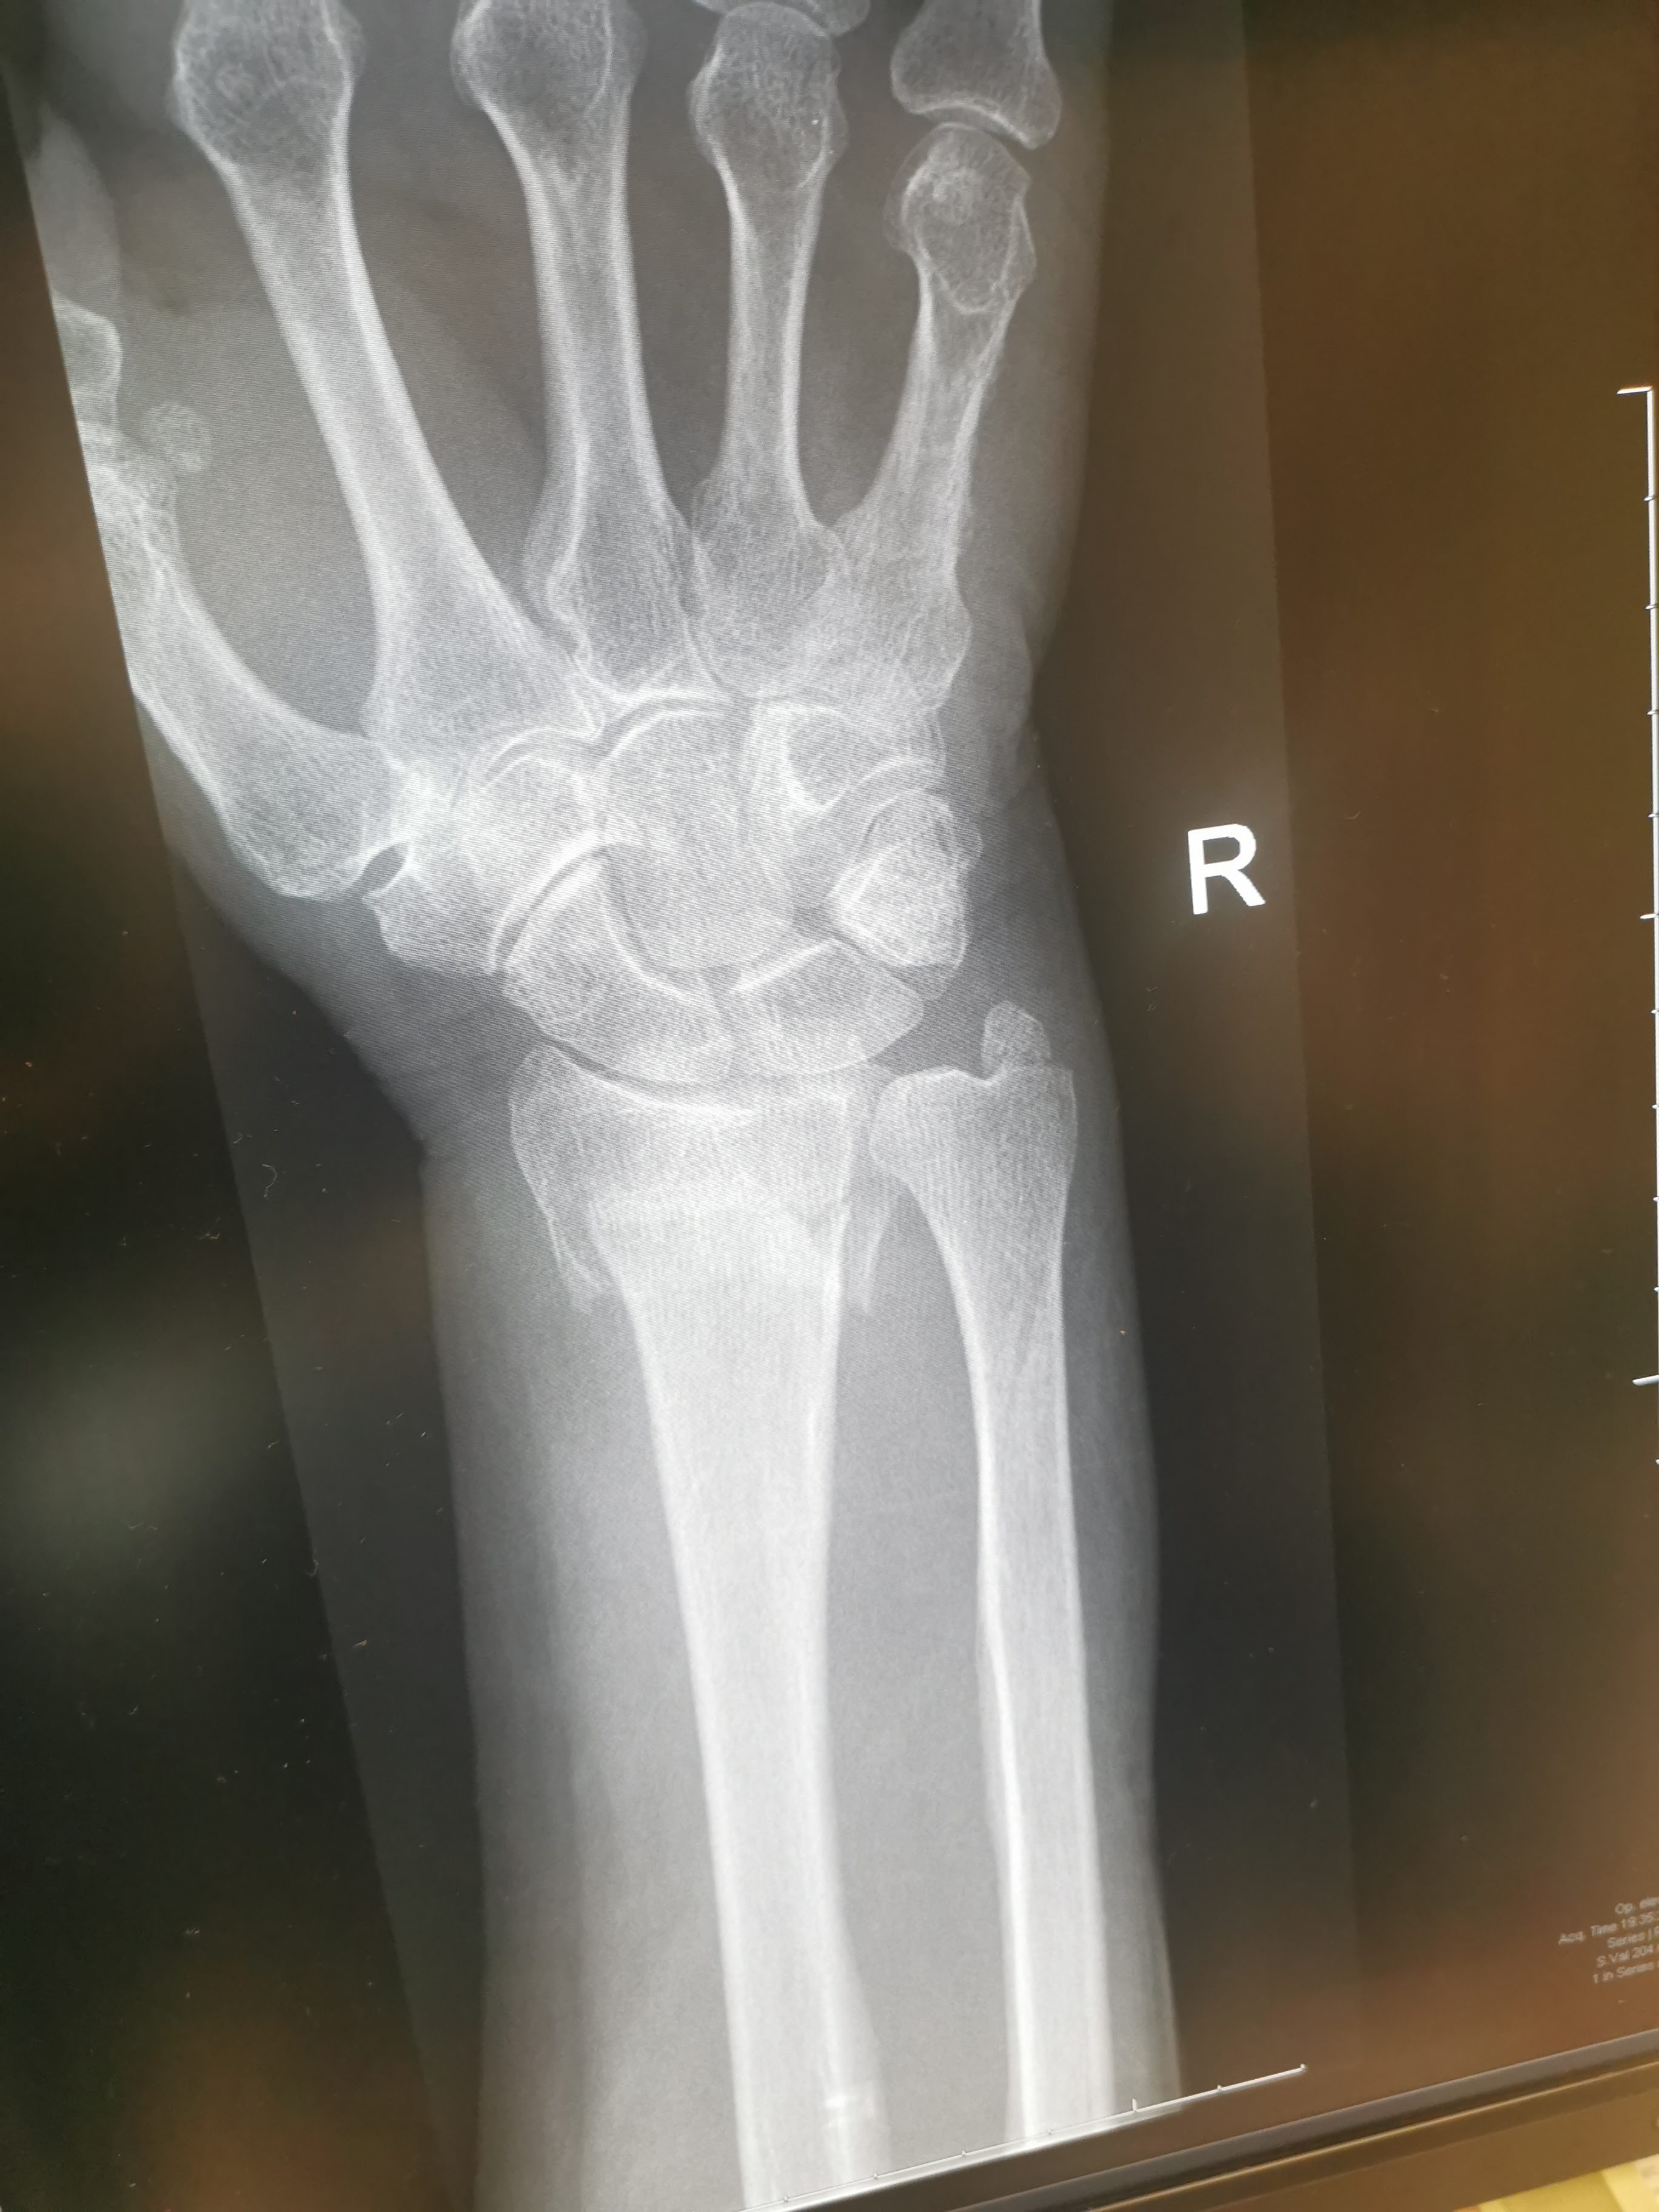

Once we had made our way back down the hill and to the motorhome I helped Sarah change into warm dry clothes. We then drove to Taupo Hospital who were fantastic seeing Sarah almost immediately and after an Xray confirming the break took her into a private room before knocking her out to pull the wrist back into place and placing it in a cast. Afterwards they told us that the wrist needed to be properly set and that most likely a plate would be needed. We could either drive to Rotorua the following day or return to Auckland. We made the decision that we would return to Auckland in the morning.

Sure, enough once we had waded our way through the bureaucracy that is the medical system in New Zealand an appointment at Greenlane Orthopedic clinic was secured a couple of days later. Another Xray followed, then a long wait to see one of the doctors who confirmed that the wrist had been badly broken but the extent of the break would require a CT scan which could only be done at Auckland Hospital. Fighting the motorway traffic we arrived at Auckland hospital thinking that everything would be in place after the referal from Greenlane, but no, another hours long wait for the CT scan and an even longer wait for another doctor.

Once this had finally been done and analysed and checked by a senior doctor, it was confirmed that surgery to fit a plate was required. The next discussion was whether the surgery would be done at Auckland or Manukau hospital (where there is a specialist hand unit). In the end they opted to do things at Auckland Hospital. At which point they sent us home for the night with instructions to return the following day for the surgery.